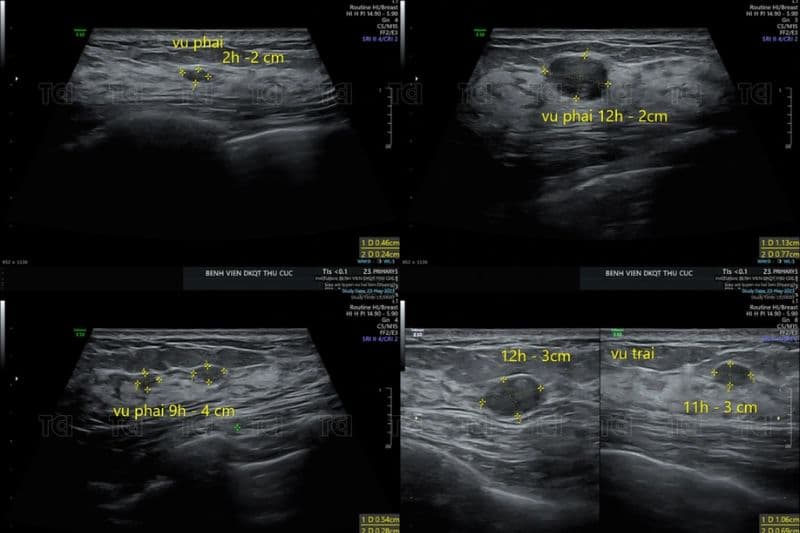

2. Hình ảnh siêu âm vú phát hiện bệnh gì?

Khi tìm hiểu siêu âm vú phát hiện bệnh gì, nhiều người thường nghĩ ngay đến ung thư. Tuy nhiên, trên thực tế, phần lớn tổn thương phát hiện qua siêu âm là lành tính.

2.1. Siêu âm vú phát hiện bệnh gì: Các bệnh lý lành tính của tuyến vú

Nang vú là tổn thương phổ biến, thường xuất hiện dưới dạng túi chứa dịch, có bờ tròn đều và hình ảnh trống âm bên trong.

U xơ tuyến vú cũng là bệnh lý thường gặp trên siêu âm, đặc biệt ở phụ nữ trẻ. Biểu hiện là khối đặc, giới hạn rõ, ít xâm lấn mô xung quanh.

Trong các trường hợp này, hình ảnh siêu âm u vú lành tính thường có bờ đều, cấu trúc đồng nhất và không gây biến dạng mô kế cận.

Siêu âm có giá trị quan trọng trong đánh giá tổn thương nghi ngờ ác tính. Các đặc điểm gợi ý ung thư thường bao gồm khối có bờ không đều, tua gai, cấu trúc giảm âm không đồng nhất và có thể kèm hạch nách bất thường.

Trong trường hợp này, hình ảnh siêu âm u vú ác tính thường cho thấy sự xâm lấn vào mô xung quanh hoặc làm biến dạng cấu trúc tuyến vú.